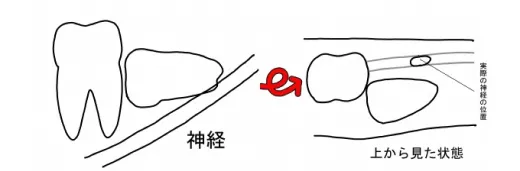

CT撮影では何が分かるのか?

4.根の先が神経や上顎洞からどのくらい離れているのか診断できる

5.埋伏している歯がどこにあるか正確に分析できる